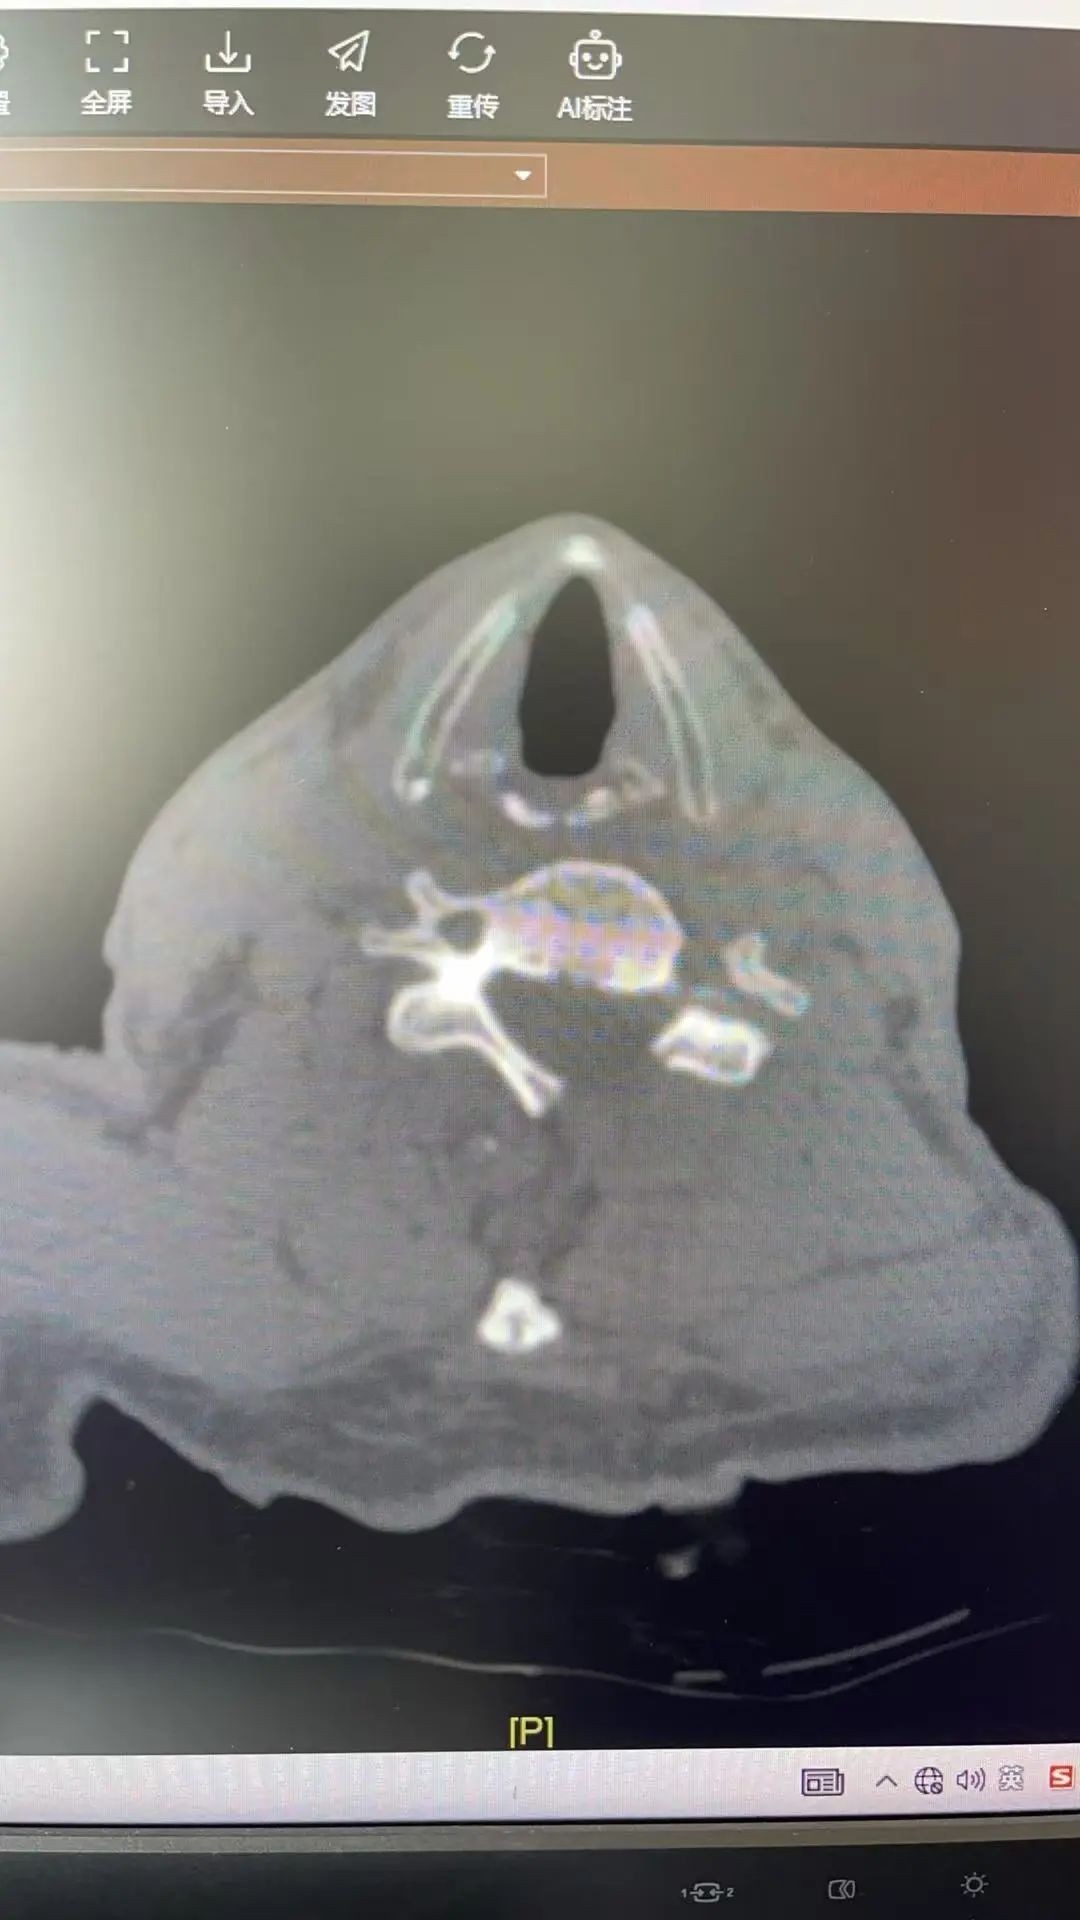

▲术后CT影像

2月27日清晨,手术由赵斌修主任医师和潘华文主治医师进行,通过UBE内镜系统,病人病灶的图像在屏幕上放大数倍而纤毫毕现,赵斌修团队运用超高速磨钻以毫米级精度“雕刻”骨化黄韧带,神经剥离器轻柔推开粘连组织……两个仅1厘米的切口,完成了过去需10厘米切口才能实现的精准减压。

术后当晚,赵斌修主任医师查看病人术后情况,陈伯四肢活动良好,并诉说下肢的麻木感明显减轻,双手也变得如以前一样灵巧,不再笨拙;次日清晨,他在搀扶下迈出第一步,泪水夺眶而出:“我以为这辈子只能卧床了……”。数日后病人出院,当天,陈伯激动地握住赵斌修主任的双手:“这次手术,治了我的病,更是救了我们这个家!”